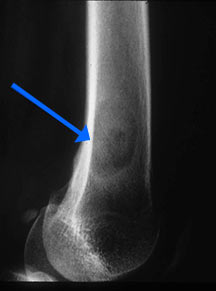

- Radiographically variable appearance: may appear benign (geographic) or malignant (permeative or moth eaten)

Radiographic Presentation